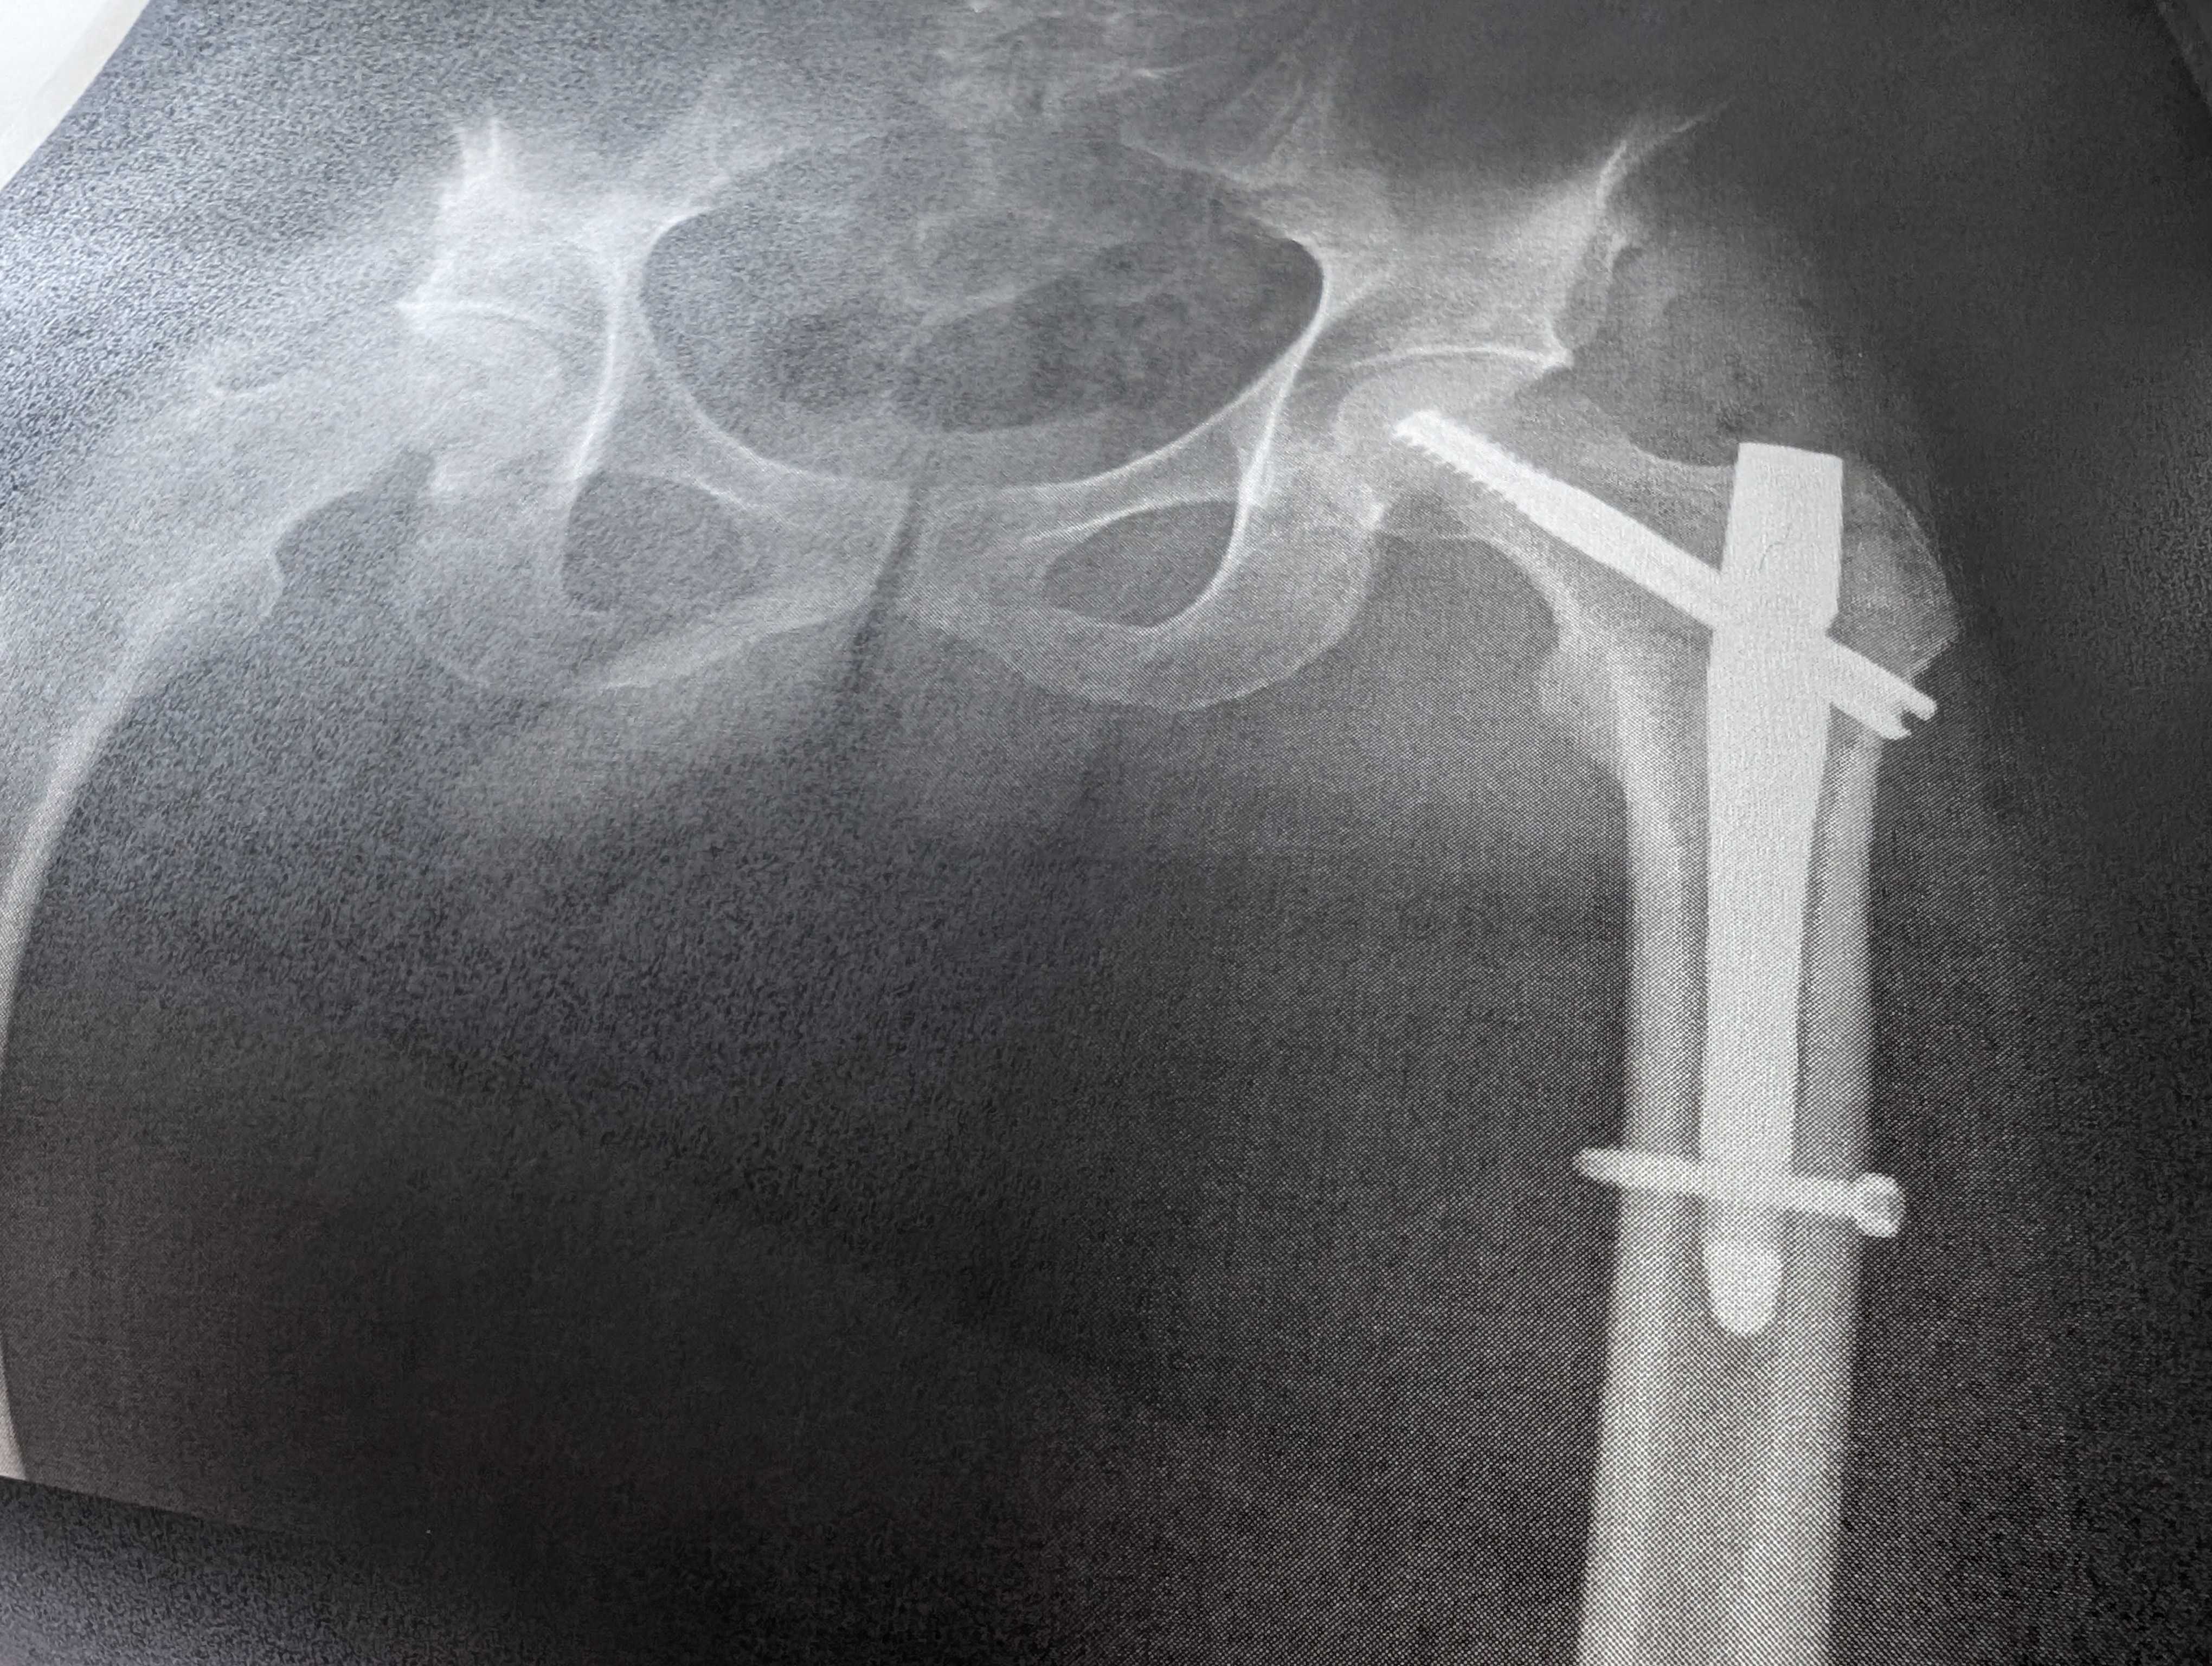

笠間ヒルクライムで落車し左大腿骨を骨折。

コース終盤左コーナーをダンシングしたら前日の雨で濡れた路面で滑り左半身強打。立ち上がるも再乗できず自転車を支えにゆっくり歩いてゴール。

打撲かなと思ったが脚を持ち上げられず折れてるかもと。

救急車で運ばれた茨城県立中央病院で骨折の診断。

昔左下腿を骨折しその時は金属を入れてその後抜いたが大腿は金属を入れたままになると。

翌日朝の手術となり手術後直ぐにリハビリを開始して順調なら2~3週でゆっくり歩けるようになるのでそこでリハビリ転院という流れ。

手術は予定より長く3時間くらいか。